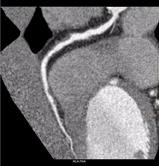

Initial interpretation suggested the presence of a two-vessel disease: There was plaque in the proximal left anterior descending (LAD) (the curved multi-planar reformation is shown in Figure 1a) and also the mid-portion of the right coronary artery (RCA) (the curved multi-planar reformation is shown in Figure 1b). Myocardial Defect Assessment was performed. (An overview of the results is shown in Figure 2.)